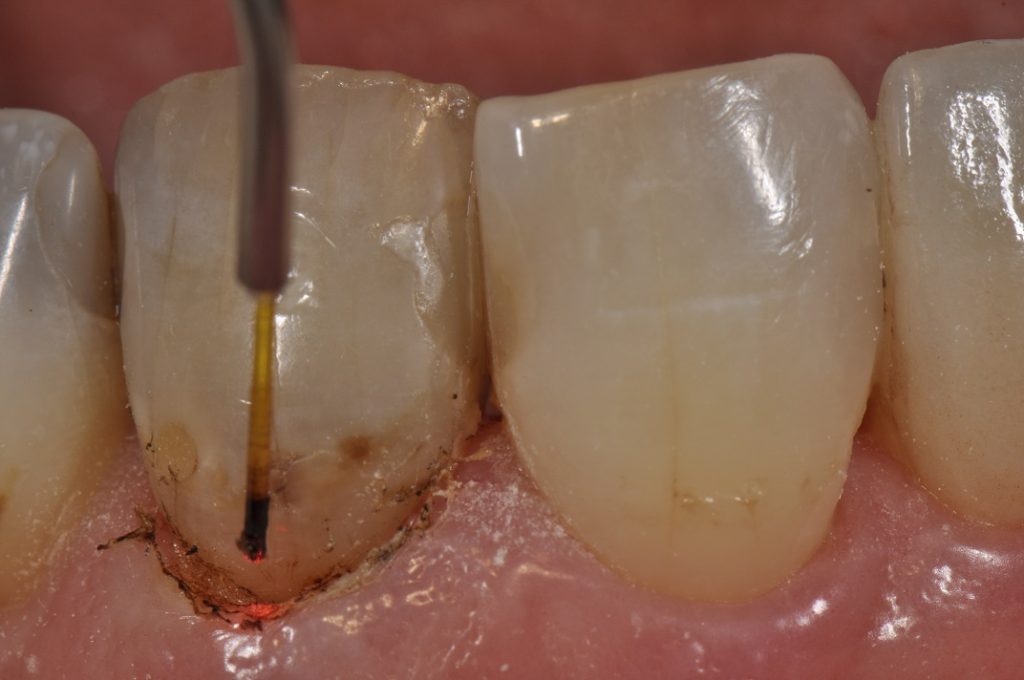

The amazing Ultradent Gemini diode laser (810nm and 980nm) was used to adjust the gingival margins prior to a transsulcular osseous recontouring approach using the Kois Wedelstaedt chisel (Brasseler USA), re-establishing the 3mm biologic width mid-facially and 4mm at the proximofacial line angles. The Gemini uses different wavelengths for different therapeutic actions – 980nm is attracted to the water content more resulting in more efficient coagulation and cutting. It has been used in pain relief and inflammation reduction protocols. 810nm requires carbonization of the tip to account for its lesser absorption (10 times less than 980nm) but is an efficient “cutter”). Probably the most powerful and efficient cutting I have seen from any diode to date. After soft tissue resolution in approximately 3 weeks, we will be able to proceed with resin bonding on a case that is now more likely to be balanced to the eye.